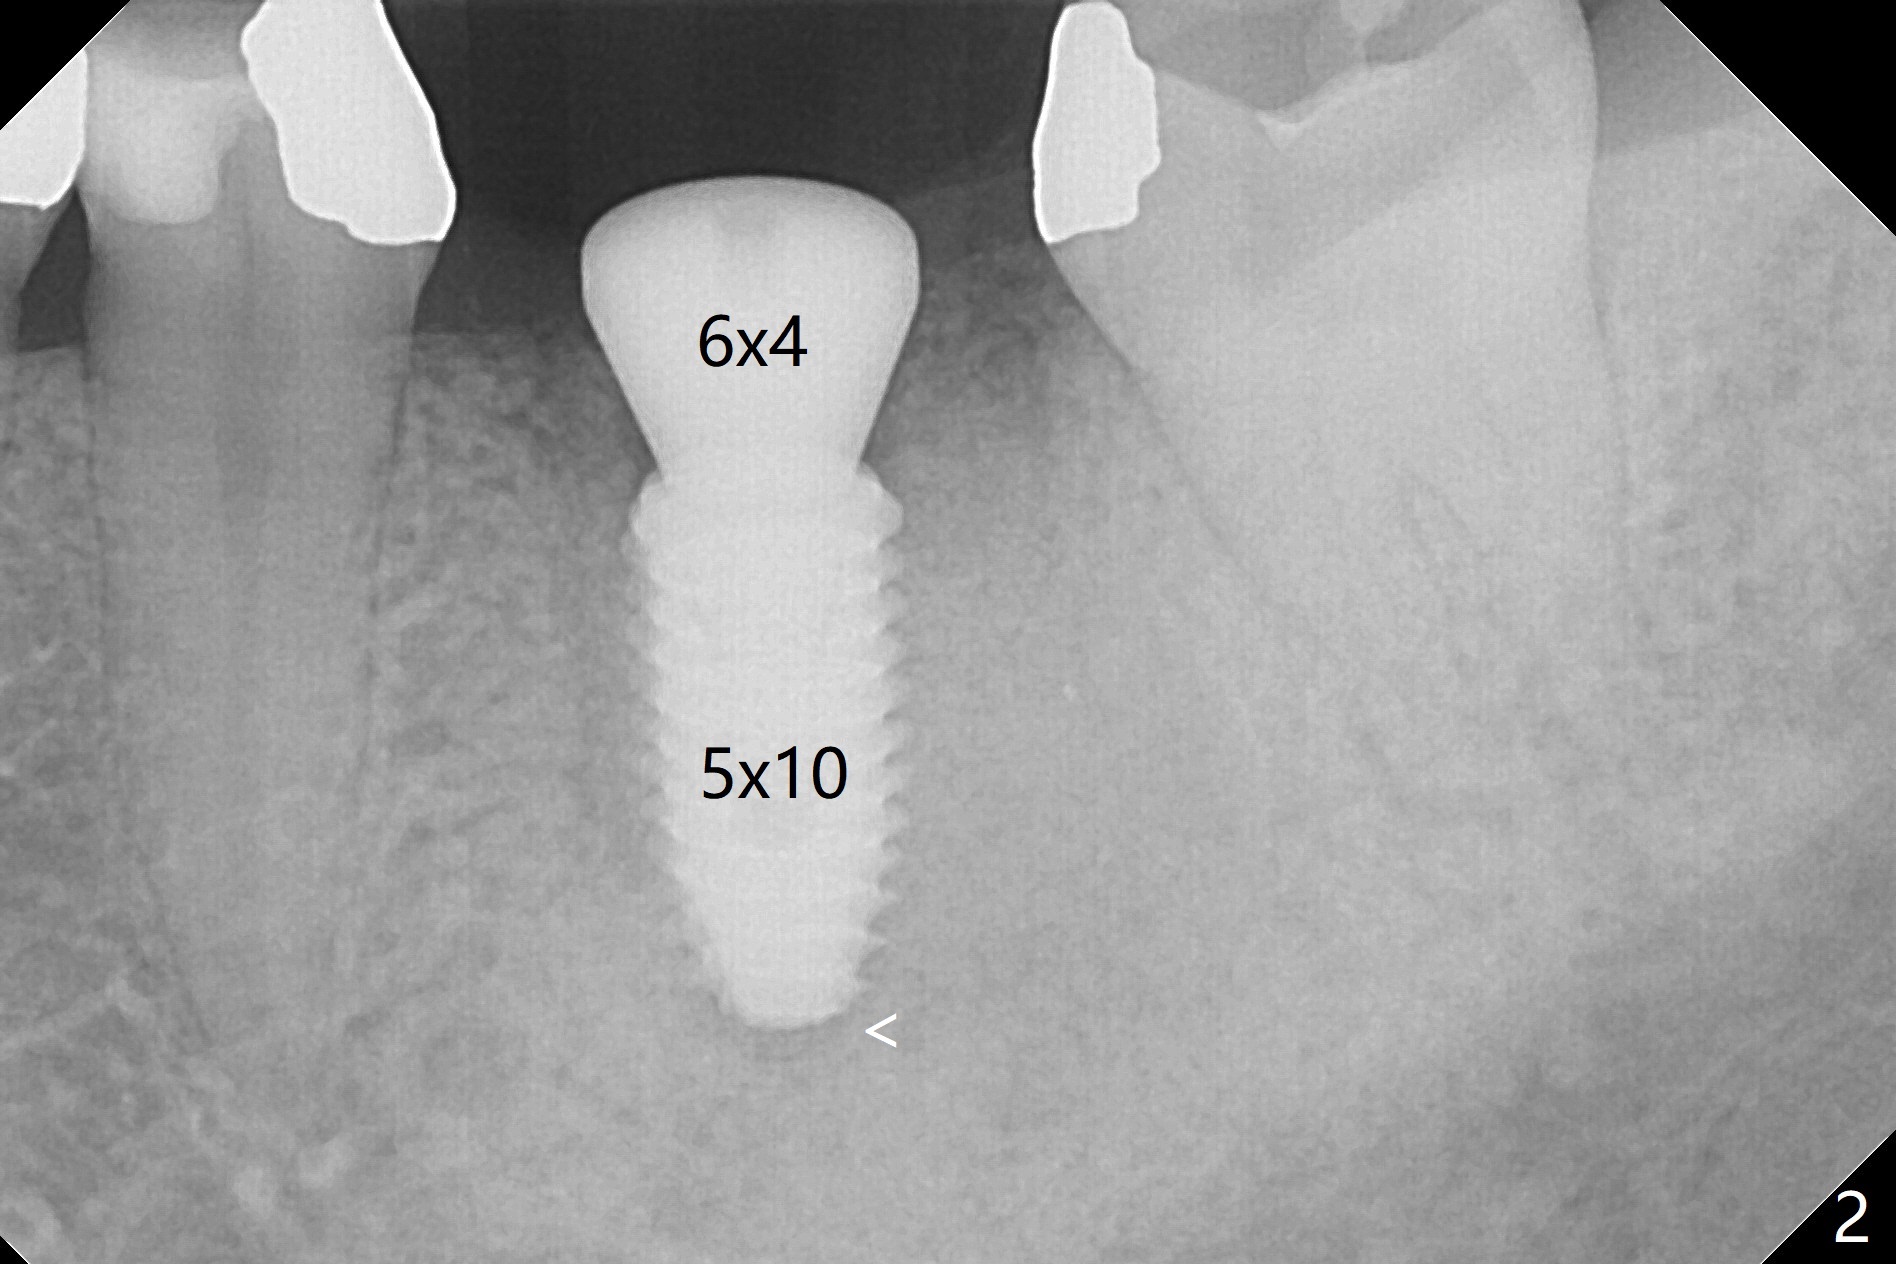

The ridge at #19 is slightly atrophic 5 months post socket preservation (Fig.1). The bone is long enough to hold a 11.5 mm long implant. There is no difficulty in inserting the corresponding drill (4.5x11.5 mm) into the metal sleeve, but the lower right posterior teeth prevent the implant handpiece from going downward completely when the handpiece accesses lingually. Because of the extra manipulation, a 5x10 mm implant achieves insertion torque of ~ 20 Ncm (Fig.2). The implant seems to be seated in the middle of the ridge (Fig.3). The bone density mesial to the implant increases 5 months postop (Fig.4), whereas that distal to the implant remains low 9 months postop (Fig.5). Bitewings taken 2.5 months post cementation (1 year postop, Fig.6,7) show subcrestal placement of the implant (advantage of guided surgery). The implant appears to be well protected; the crestal bone seems to cover the implant plateau. There will be little chance of thread exposure over years of use. The trabecular pattern around the implant is similar to that around the roots of the tooth #30 one year 7 months post cementation (2 years 4 months postop, Fig.8).